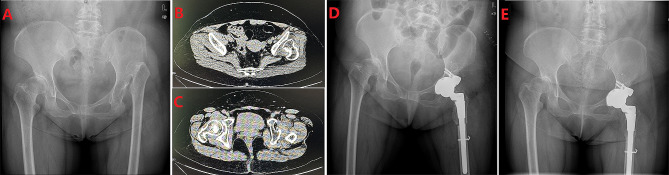

Fig. 2.

Pre- and postoperative radiographs of a woman with left Crowe type IV DDH. (A) Preoperative pelvic radiograph of a 60-year-old female patient with left Crowe type IV developmental dysplasia of the hip (DDH). (B) CT image shows the position of the left false acetabulum. (C) CT image shows bilateral true acetabulum position. (D) Postoperative pelvis radiograph demonstrating left acetabular reconstruction using a TM pads, and femoral shortening osteotomy on each side. (E) six years post-surgery, the pelvic X-ray revealed no evidence of loosening or absorption on the acetabular side and complete osseous integration on the femoral side without any subsidence